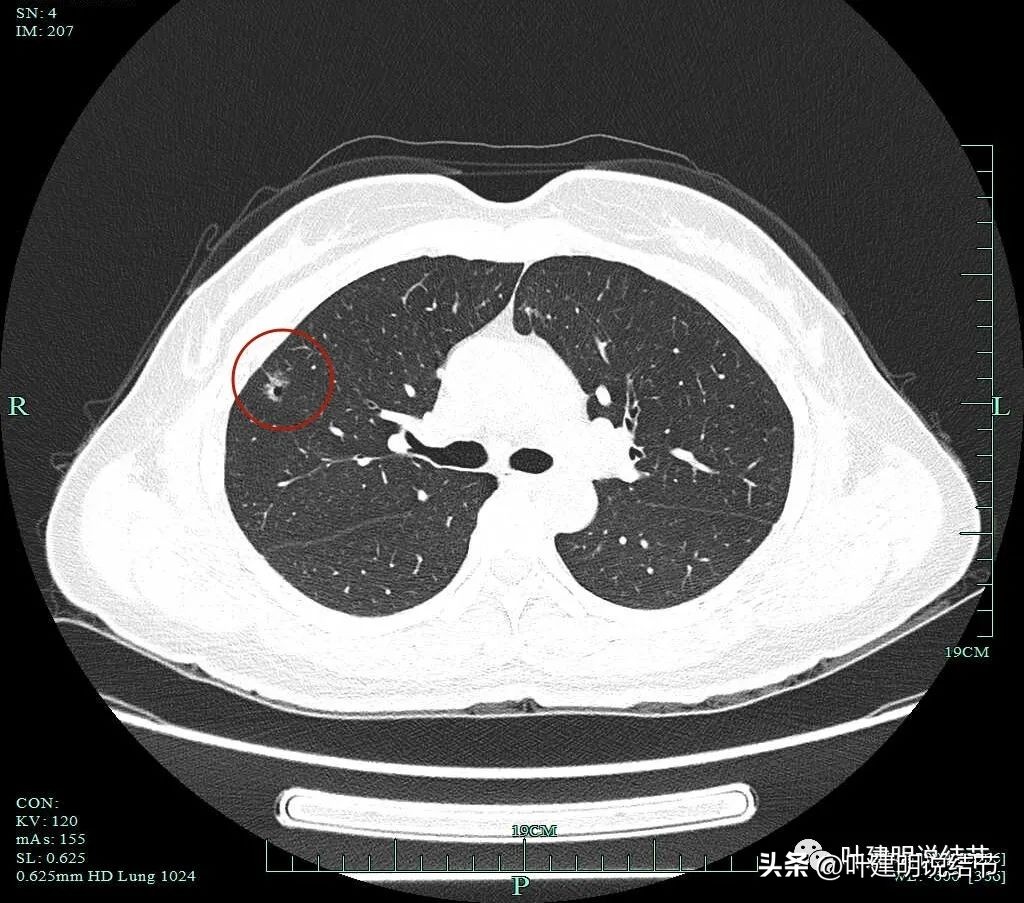

上图示病灶1的定位,红色箭头示病灶1,绿色箭头示定位医用胶。

上两图示病灶2的定位:红色箭头示病灶2,绿色箭头示医用胶。层厚1.25毫米,两者相差5层,也就是说上下相差6.25毫米,术中见到医用胶后,病灶在其下方6.25毫米。